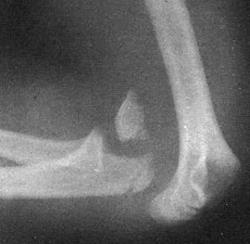

Вывих предплечья

Вывих предплечья - это смещение суставных поверхностей локтевой, лучевой и плечевой кости относительно друг друга. Повреждение сопровождается резкой болью, деформацией и значительным отеком сустава. Движения невозможны. Диагноз устанавливается на основании данных осмотра и результатов рентгенологического исследования. При необходимости уточнения характера травмы дополнительно выполняется МРТ или КТ. Лечение вывихов предплечья осуществляется путем их вправления и последующей фиксации сустава гипсовой повязкой в течение 2-3 недель. После снятия гипса проводится восстановительная терапия : физиолечение, массаж, ЛФК.

Вывих предплечья занимает второе место по частоте и составляет от 18 до 27% от общего числа вывихов. У детей вывих предплечья встречается чаще, нередко сочетается с переломом костей плеча и предплечья. Вывих предплечья может быть неполным (суставные поверхности частично соприкасаются) или полным (соприкосновение суставных поверхностей отсутствует). В абсолютном большинстве случаев (более 90%) в результате травмы вывихиваются обе кости предплечья. Изолированные вывихи одной из двух костей предплечья наблюдаются редко.

Задний вывих

Возникает в результате непрямой травмы (падения на переразогнутую в локтевом суставе вытянутую руку). Капсула локтевого сустава при этом разрывается, нижняя часть плеча смещается вперед. Задний вывих предплечья может сочетаться с переломом мыщелков плечевой кости у взрослых или с переломом надмыщелков плеча у детей.

Пациент с задним вывихом предплечья жалуется на резкую боль в области повреждения. Рука находится в вынужденном положении легкого сгибания. Сустав деформирован, увеличен в объеме, активные движения в локтевом суставе невозможны, при попытке пассивных движений определяется характерное пружинящее сопротивление. При осмотре спереди предплечье выглядит укороченным. Локтевой отросток смещен кверху и кзади. В области локтевого сгиба пальпируется нижняя часть плечевой кости.